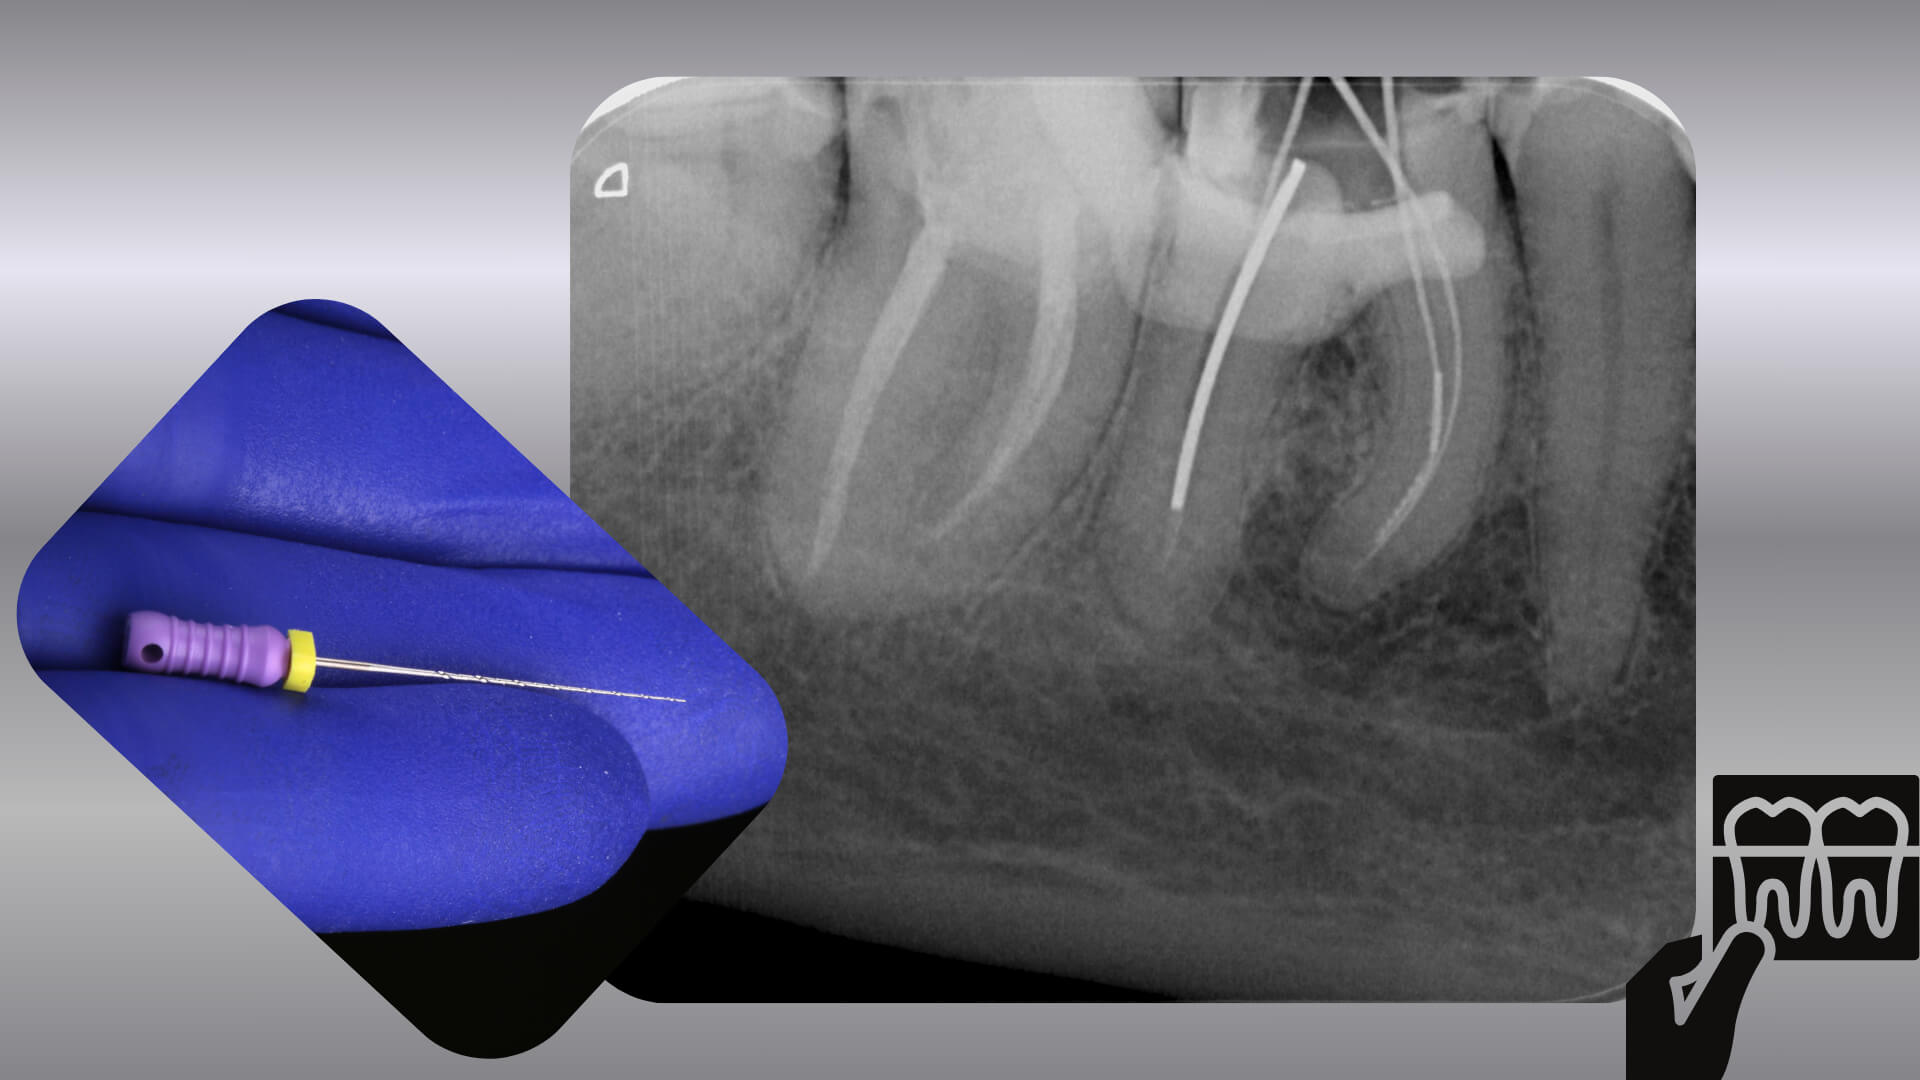

Złamane narzędzie w kanale – jak tego uniknąć i co zrobić, gdy już się stanie?